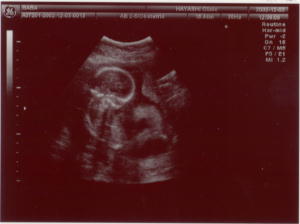

12/3は診察の日でした。

超音波では頭の輪郭からのびる背骨も見えました。元気に育ってるとの事。

中期の血液検査もしました。

今度は正月明け。性別分かるかも。3Dもあります。栄養指導もあるらしい。